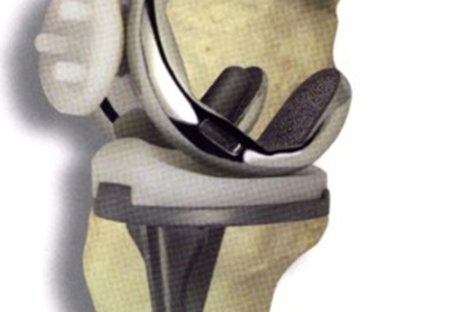

I Norge brukes vanligvis sementerte kneproteser uten kneskjellskomponent (uten patellakomponent figur 1 og 2:) (Figur 3 kneprotese med patellakomponent).

Figur 3: Bilde av kneprotese på plastben med patellakomponent). Disse protesene har gitt gode resultater, og 95 % av pasientene har fortsatt sin protese i kneet etter 10 år (Art_Dyrhovden-Have the causes of.pdf).